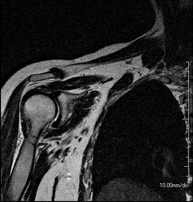

- Shoulder MRI

Examination to study injuries to tendons, muscles and joints. Its main use is to diagnose injuries to the rotator cuff tendons. It lasts approximately 20 minutes. It is a radiation-free procedure.